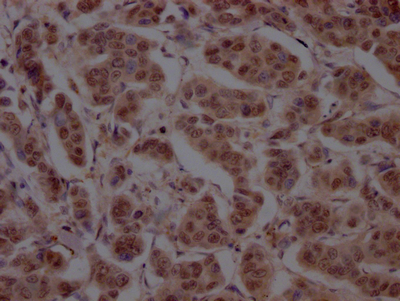

IHC image of CSB-RA898115A0HU diluted at 1:100 and staining in paraffin-embedded human breast cancer performed on a Leica BondTM system. After dewaxing and hydration, antigen retrieval was mediated by high pressure in a citrate buffer (pH 6.0). Section was blocked with 10% normal goat serum 30min at RT. Then primary antibody (1% BSA) was incubated at 4℃ overnight. The primary is detected by a Goat anti-rabbit IgG polymer labeled by HRP and visualized using 0.05% DAB.

IHC image of CSB-RA898115A0HU diluted at 1:100 and staining in paraffin-embedded human prostate cancer performed on a Leica BondTM system. After dewaxing and hydration, antigen retrieval was mediated by high pressure in a citrate buffer (pH 6.0). Section was blocked with 10% normal goat serum 30min at RT. Then primary antibody (1% BSA) was incubated at 4℃ overnight. The primary is detected by a Goat anti-rabbit IgG polymer labeled by HRP and visualized using 0.05% DAB.